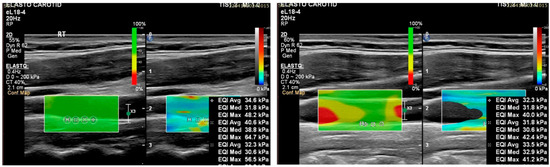

- A 2D color map of the shear wave velocities (SWVs) should be acquired, as it aids with the identification of homogeneous areas where the measurements are the most reliable. ROIs should be placed where the map shows a homogenous SWE distribution [56].

- The cine-loops should last for 10 s in a longitudinal view of the vessel (common carotid artery), approximately 2 cm from the carotid bulb, and four to five consecutive frames should be analyzed to calculate the average Young’s modulus from these frames. This approach should yield 40 Young’s modulus values per participant, that is, four ROIs times five frames times two sides [58,60,62,63].

- Regarding the study position of the Intima–Media Complex, other studies measured three ROIs, with one ROI in each area of interest, e.g., one ROI in the common carotid artery, one ROI in the internal carotid artery, and one ROI in the carotid bulb (totaling six ROIs for both the left and right sides) [43,67].

- For the ROI size, it is suggested that, for a CIMT on the CCA of 0.6 mm, an ROI of 2 mm should be used. The idea behind this is that large ROIs create heterogeneity in the measurement, while very small ROIs may introduce operator error [34,60]. Researchers may also explore in the future the use of 1 mm ROI sizes [67].

3.2. Assessing Carotid Plaques with Shear Wave Elastography